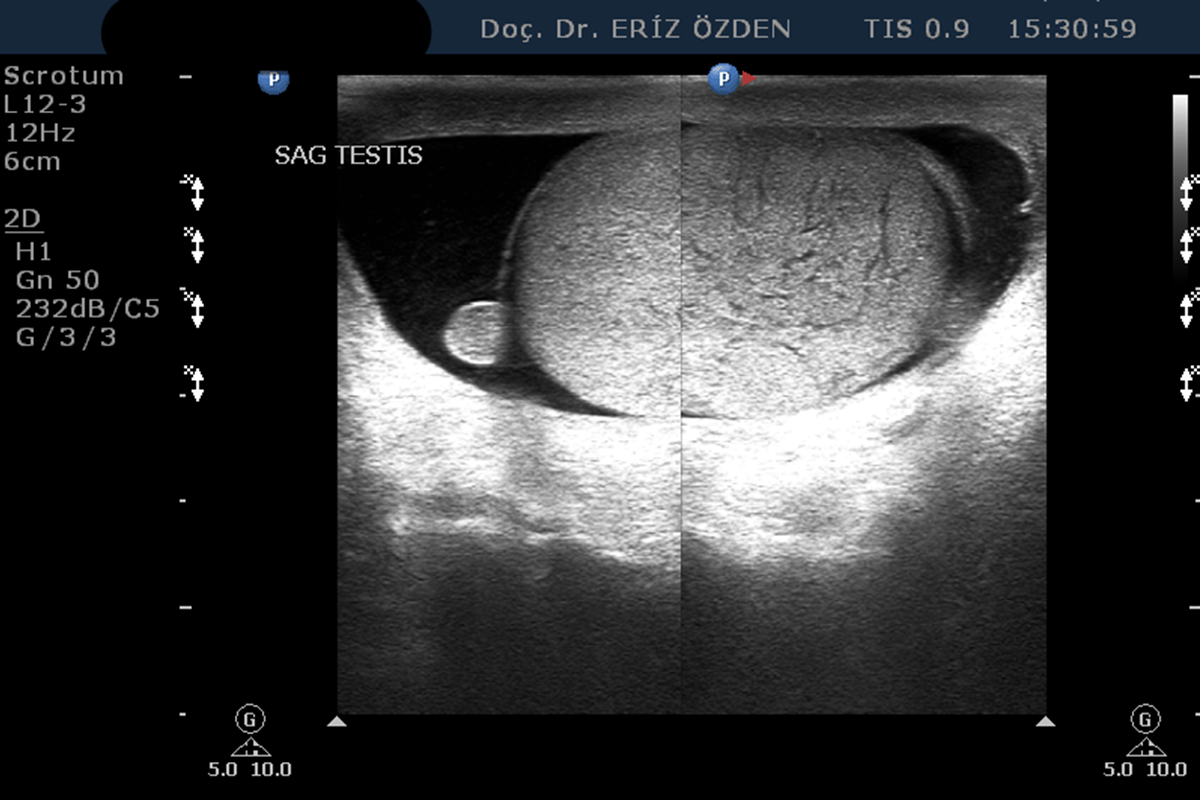

Skrotal Ultrasonografi

Erkeklerde yumurtalıkların, çevresindeki meni kanallarının ve  varikosel adı verilen damar genişlemelerinin incelenmesi için yapılır. Yumurtalık iltihapları, tümörleri, testis çevresindeki sıvı birikimleri, meni kanallarındaki kistler gibi rahatsızlıklarda ilk kullanılan görüntüleme yöntemidir. İncelemenin herhangi bir ön hazırlığı yoktur